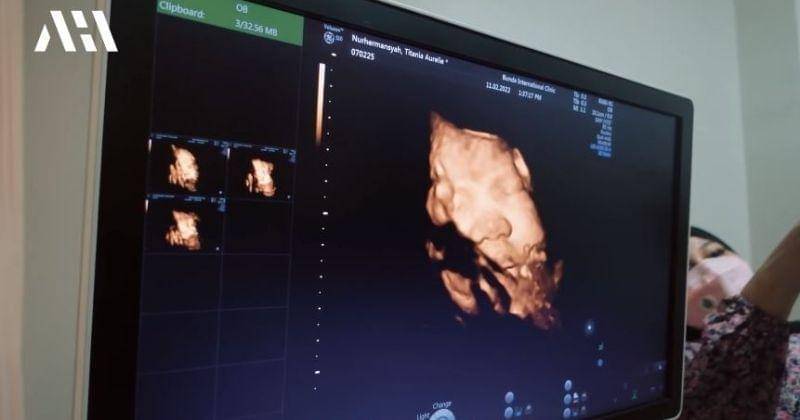

Akhirnya tiba momen di mana Aurel melakukan USG untuk melihat perkembangan dan wajah Baby A sebelum akhirnya lahir. Raut wajah penuh bahagia pun tak dapat ditutupi saat Ashanty dan Krisdayanti melihat wajah cucunya dari layar monitor hasil USG.

Saat melihat wajah Baby A, Ashanty dan Krisdayanti pun memiliki pendapat yang sama bahwa wajah Baby A begitu mirip dengan Atta.

"Mirip bapaknya banget aduh," ujar Ashanty usai melihat wajah Baby A.

"Mukanya kaya papanya banget," sambung Aurel.

"Bener-bener kaya lihat boneka hidup ya," tutur Krisdayanti, merasa gemas dengan wajah Baby A.